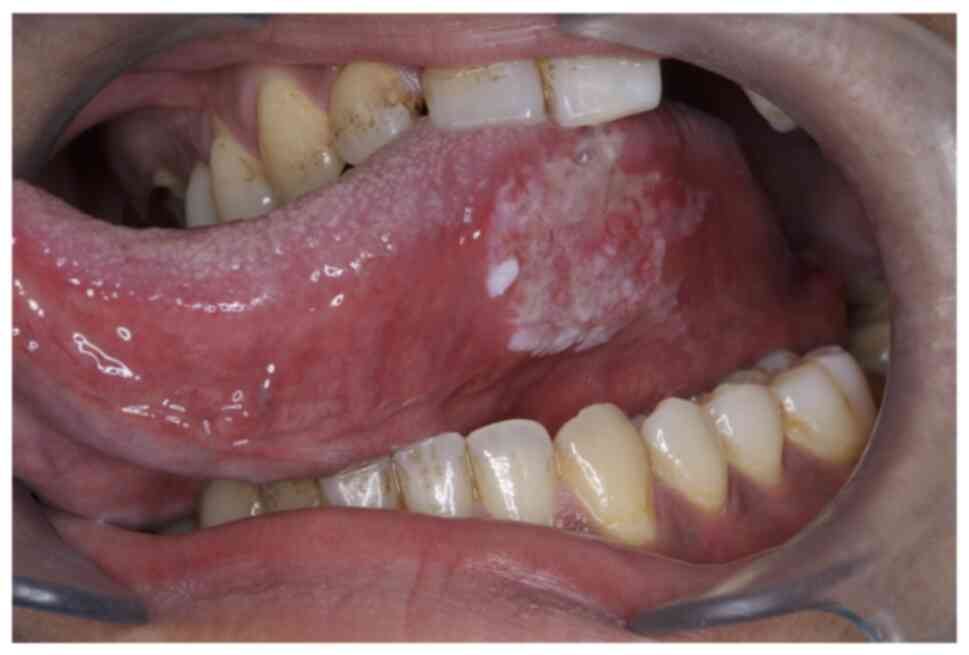

The patient appeared well-nourished and normal built, with a recorded temperature of 37.3°C. Intraoral examination revealed no sharp cusps or broken teeth, and there were no signs of traumatic occlusion or parafunctional habits. No ill-fitting dental prostheses or sharp edges of dental restorations that could cause chronic irritation to the tongue were observed. A shallow ulcer, measuring 28×20 mm in diameter, with induration and intense tenderness to touch was observed on the left lateral border of the tongue (Fig. 1). Residual leukoplakia and erythema were present around the ulcer. Extraoral examination revealed a soybean-sized swollen left submandibular lymph node with mild tenderness. The left superior internal jugular lymph node was also thumb-sized and palpable.

Figure 1.

Clinical presentation of the tongue lesion. A shallow ulcer with residual leukoplakia and erythema is observed on the left lateral border of the tongue.